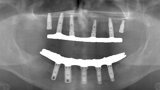

Fig. 7. Rx Pre-operatoria, Prótesis híbrida inmediata con 10 años de evolución y Rx Control a los 10 años.

Fig. 8. Rx Pre-operatoria, Prótesis híbrida inmediata con 10 años de evolución y Rx Control a los 10 años.

Fig. 9. Rx Pre-operatoria, Prótesis híbrida inmediata con 10 años de evolución y Rx Control a los 10 años.